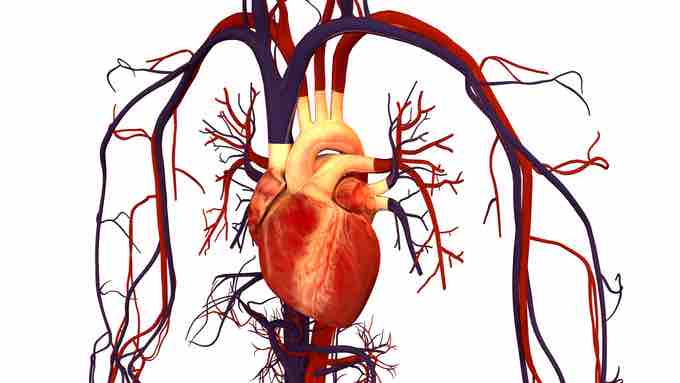

At the core of the human circulatory system is the heart . The size of a clenched fist, the human heart is protected beneath the rib cage. Made of specialized and unique cardiac muscle, it pumps blood throughout the body and to the heart itself. Heart contractions are driven by intrinsic electrical impulses that the brain and endocrine hormones help to regulate. Understanding the heart's basic anatomy and function is important to understanding the body's circulatory and respiratory systems.

Human heart

The heart is central to the human circulatory system, as it pumps blood throughout the body.